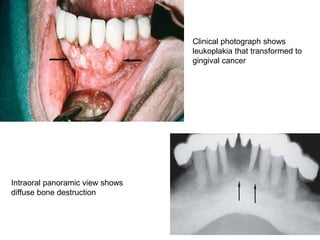

Clinical photograph shows

leukoplakia that transformed to

gingival cancer

Intraoral panoramic view shows

diffuse bone destruction